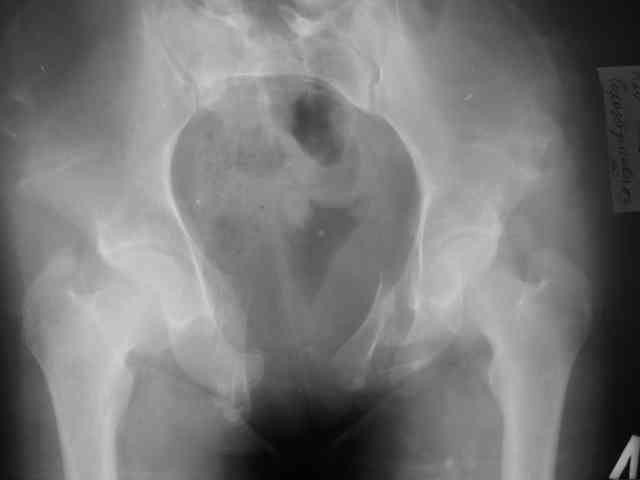

Предоставляю Вашему вниманию неотдаленный результат лечения (5 месяцев) 20 летней девушки с переломом костей таза.

Укорочение левой нижней конечности 2 см.

Снимки в 2 проекциях прилагаются.